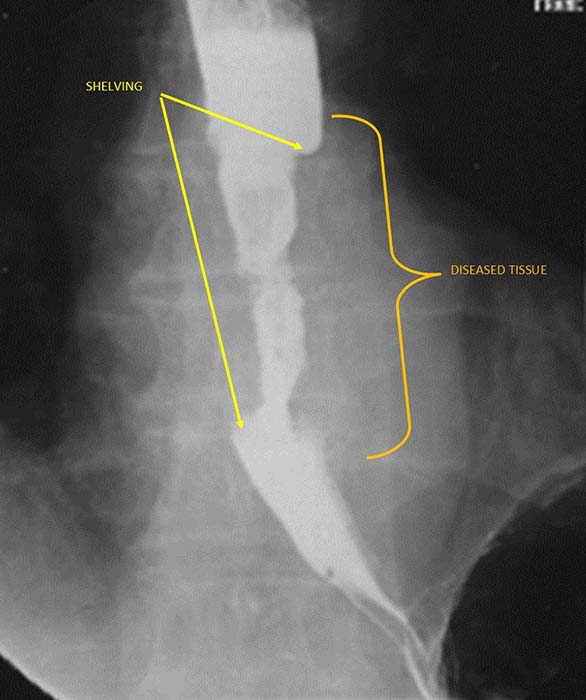

What is 'shelving' in esophageal carcinoma?

Sharp, shelf-like demarcation between normal and diseased esophagus (classic infiltrative sign).

What are the two growth patterns of esophageal carcinoma?

Infiltrating and proliferating.

What is the radiographic appearance of the infiltrating type of esophageal carcinoma?

Irregular narrowing, mucosal destruction, esophageal dilation above lesion.

What are the best imaging studies for esophageal carcinoma?

Barium swallow (if patient can swallow); CT for staging and treatment planning.